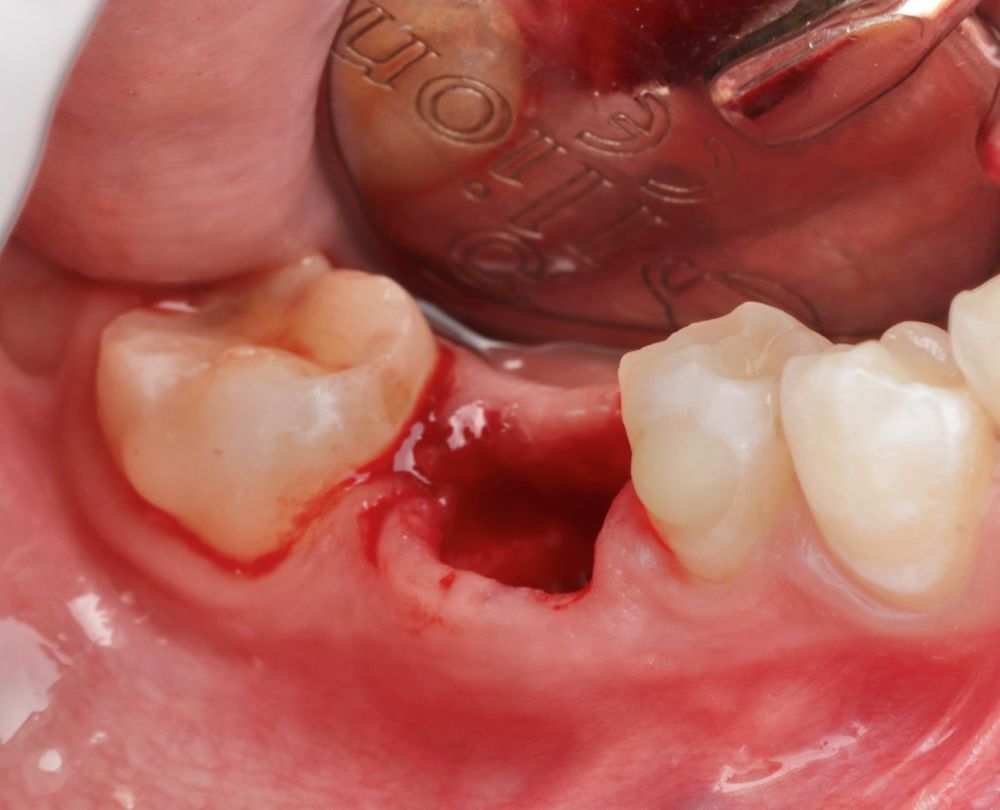

Se reporta el caso de un autotrasplante del tercer molar inferior derecho al alveolo postextracción de un primer molar inferior, en una paciente de 22 años de edad. Actualmente, el autotransplante se considera una opción de tratamiento si se siguen los criterios de selección del caso adecuados, y se realiza una técnica quirúrgica protocolizada. El diagnóstico planificado mediante CBCT, la simulación virtual y la confección de una réplica en 3D optimiza la técnica de forma segura, predecible con tiempos de cirugía menores.

La confección de la réplica 3D del diente se ha de realizar con material biocompatible y esterilizable mediante radiación gamma y beta. La ventaja del modelo estereolitográfico es minimizar el tiempo extraoral del diente donante, el daño al ligamento periodontal, así como poder remodelar el alveolo receptor sin usar el diente donante5,13,14.

Todo ello favorece un crecimiento esquelético continuo y resistencia a las cargas oclusales8,12.

Hay que tener en cuenta la anchura del hueso en sentido buco-lingual, ya que si es insuficiente puede provocar la reabsorción del reborde alveolar5,15.